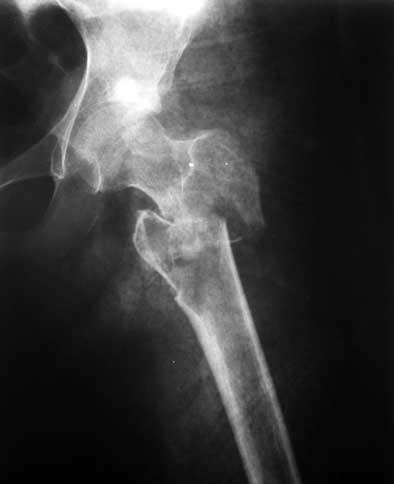

На днях - патологический перелом (первый снимок). Пока наложена кокситная повязка (второй снимок). Вопрос - как лучше вести больную? Консервативно - оставить в этой же повязке? Остеосинтез? Какой именно? Спасибо. Екатерина А. Озерова, детская ортопедическая клиника УНИИТО

(восстановление шеечно-диафизарного угла, кюрретаж полости с гистологическим исследованием материала, секвестрэктомия, повторная костная пластика и ранняя мобилизация тазобедренного сустава) судя по толщине кортикального слоя, двигательная активность у барышни и до перелома оставляла желать лучшего, поэтому ранняя нагрузка на ногу будет способствовать сращению перелома. Сложно советовать о методе фиксации - что Вы используете рутинно для фиксации подвертельных переломов -этим и следует воспользоваться.

Реконструктивные гвозди, PFN, gamma nails etc. были бы предпочтительны ввиду меньшей интраоперационной травмы для тканей и возможности ранней динамизации, способствующей мозолеобразованию.DCS или 95 град. клинковая

пластина менее предпочтительны и потребует более массивной костной пластики для замещения дефекта, расширенной диссекции мягких тканей и биомеханически не самое лучшее решение (вероятность протрузии клинка через шейку бедра и

варизации шеечно-диафизарного угла в связи с отсутствием полноценной кости по медиальному контуру проксимального отдела бедра).